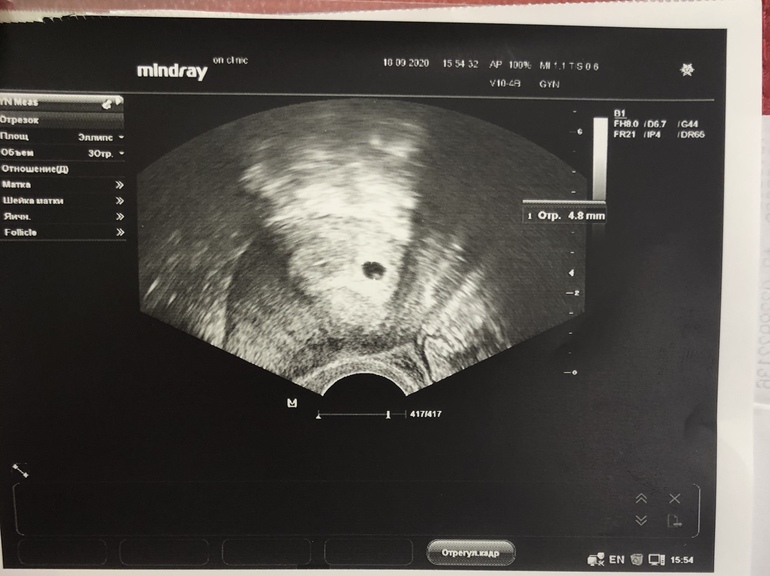

Плодное яйцо нашли! Сроку 3-4 неделям соответствует. Посмотрели что прикрепилось в самое дно матки. Ре в восторге, я в восторге. Теперь на след неделе пересдать кровь и 26 числа пойду сердечко слушать))

Меня тоже мучает вопрос когда. В среду будет полных 5 недель, а на 14 Дпо хгч 415. Сижу, думаю, будешь видно или нет

Говорят когда хгч перевалит за 1000 тогда видно. Буду ждать)